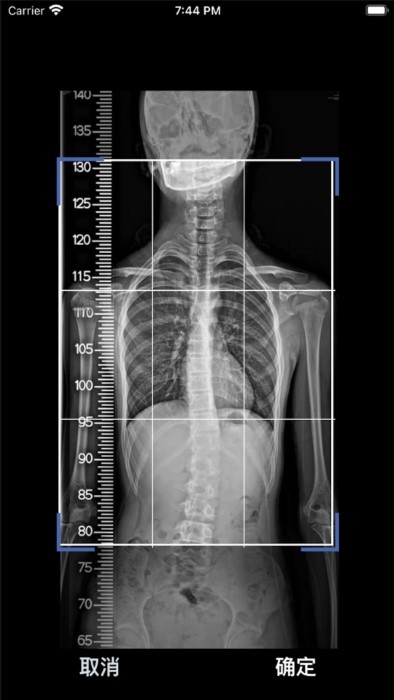

cobb角测量分析平台旨在为用户提供一种便捷、准确的脊柱角度测量工具。通过上传全脊柱X光片的正位片,软件能够自动识别并测量脊柱的cobb角,为医生提供直观的测量结果和图像显示,从而辅助医生进行脊柱侧弯等疾病的诊断和治疗。

1. 影像图片上传:用户可以通过软件上传全脊柱X光片的正位片,软件将自动识别并进行分析。

2. cobb角测量:软件将自动测量脊柱的cobb角,并在界面上显示测量结果和图像。

2. 上传影像图片:打开软件后,点击上传按钮,选择全脊柱X光片的正位片进行上传。

3. 等待自动测量:软件将自动识别并测量脊柱的cobb角,用户只需等待片刻即可查看测量结果。

4. 查看测量结果:测量结果将在软件界面上显示,用户可以根据结果进行进一步的分析和判断。